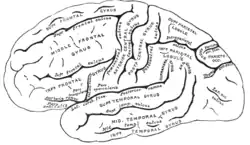

O cérebro, que consiste nos hemisférios cerebrais, forma a maior parte do encéfalo e recobre as outras estruturas cerebrais[6] A região externa dos hemisférios, o córtex cerebral, é a massa cinzenta, consistindo de camadas corticais de neurônios. Cada hemisfério é dividido em quatro lobos principais - o lobo frontal, o lobo parietal, o lobo temporal e o lobo occipital.[7] Três outros lobos são incluídos por algumas fontes, que são um lobo central, um lobo límbico e um lobo insular.[8] O lobo central compreende o giro pré-central e o giro pós-central e está incluído, pois forma um papel funcional distinto.[8][9]

O cérebro é a maior parte do encéfalo e é dividido em hemisférios direito e esquerdo quase simétricos por um sulco profundo, a fissura longitudinal.[14] A assimetria entre os lobos é observada como uma petália.[15] Os hemisférios são conectados por cinco comissuras que abrangem a fissura longitudinal, a maior delas é o corpo caloso.[6] Cada hemisfério é convencionalmente dividido em quatro lobos principais; o lobo frontal, o lobo parietal, o lobo temporal e o lobo occipital, nomeados de acordo com os ossos do crânio que os cobrem.[7] Cada lobo ou lóbulo está associado a uma ou duas funções especializadas, embora haja alguma sobreposição funcional entre elas.[16] A superfície do cérebro é dobrada em cristas (giros) e ranhuras (sulcos), muitos dos quais são nomeados geralmente de acordo com sua posição, como o giro frontal do lobo frontal ou o sulco central, que separa as regiões centrais dos hemisférios. Existem muitas pequenas variações nas dobras secundárias e terciárias.[17]

O córtex é mapeado por divisões em cerca de cinquenta áreas funcionais diferentes, conhecidas como áreas de Brodmann, que são nitidamente diferentes quando vistas ao microscópio.[20] O córtex é dividido em duas áreas funcionais principais - um córtex motor e um córtex sensorial.[21] O córtex motor primário, que envia axônios para os neurônios motores no tronco cerebral e na medula espinhal, ocupa a parte posterior do lobo frontal, diretamente na frente da área somatossensorial. As áreas sensoriais primárias recebem sinais dos nervos e tratos sensoriais por meio de núcleos de retransmissão no tálamo. As áreas sensoriais primárias incluem o córtex visual do lobo occipital, o córtex auditivo em partes do lobo temporal e o córtex insular e o córtex somatossensorial no lobo parietal. As partes restantes do córtex são chamadas de áreas de associação, que recebem informações das áreas sensoriais e partes inferiores do cérebro e estão envolvidas nos complexos processos cognitivos de percepção, pensamento e tomada de decisão.[22] As principais funções do lobo frontal são controlar a atenção, o pensamento abstrato, o comportamento, as tarefas de resolução de problemas e as reações físicas e a personalidade.[23][24] O lobo occipital é o menor lobo; suas principais funções são recepção visual, processamento visual-espacial, movimento e reconhecimento de cores.[23][24] Existe um lóbulo occipital menor no lobo conhecido como cúneo. O lobo temporal controla as memórias auditivas e visuais, a linguagem e um pouco da audição e da fala.[23]